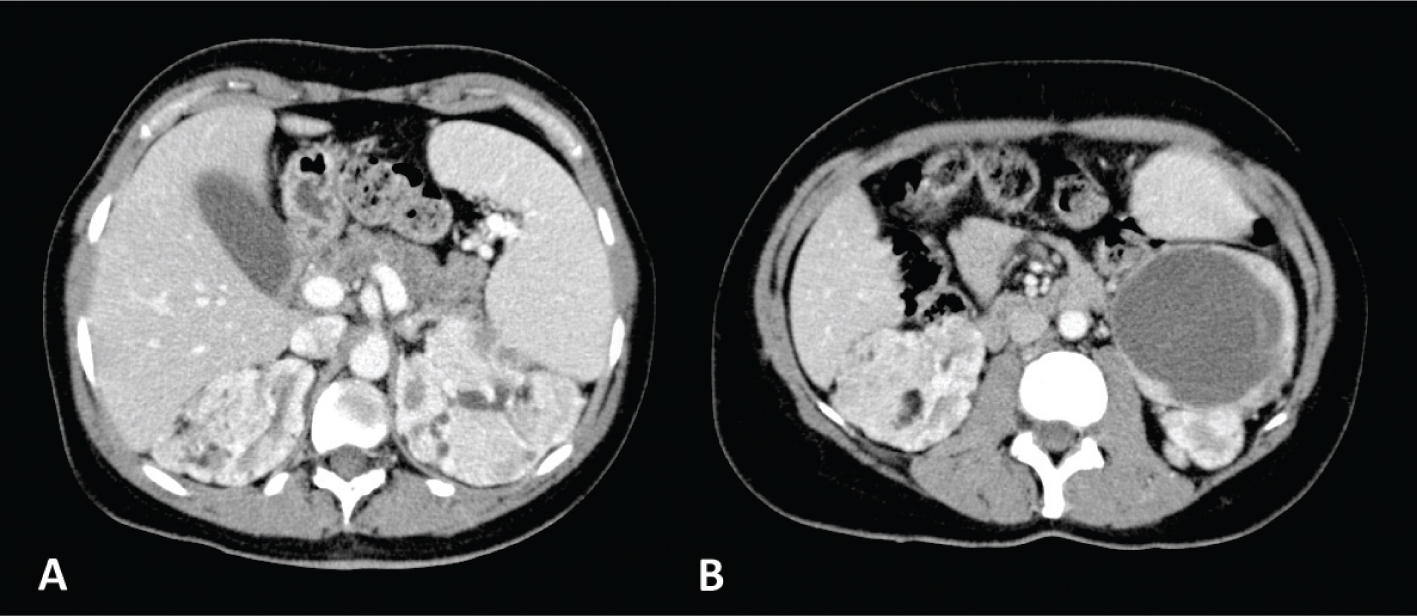

On magnetic resonance imaging (MRI), it appears isointense compared with fat on T1-weighted images; moreover, with the use of in-phase and opposed-phase imaging, AMLs with predominant adipose component show the characteristic India ink artifact that appears at the interface between the lesion and the normal renal parenchyma on opposed-phase T1-weighted images. In T2-weighted images, however, the intensity can be variable, depending on the amount of adipose tissue present in the lesion, resulting homogeneously high in AMLs with a higher adipose component (Figure 2) (5154).

Fig 2

Figure 2. MRI axial scan of the abdomen shows two AMLs of the left kidney. (A) Opposed-phase shows the characteristic India ink artifact of the AMLs. (B) AMLs appear hyperintense on T2-weighted images and (C) hypointense on T2-weighted images with fat suppression. (D) T1-weighted image with fat suppression shows contrast enhancement of the AMLs.